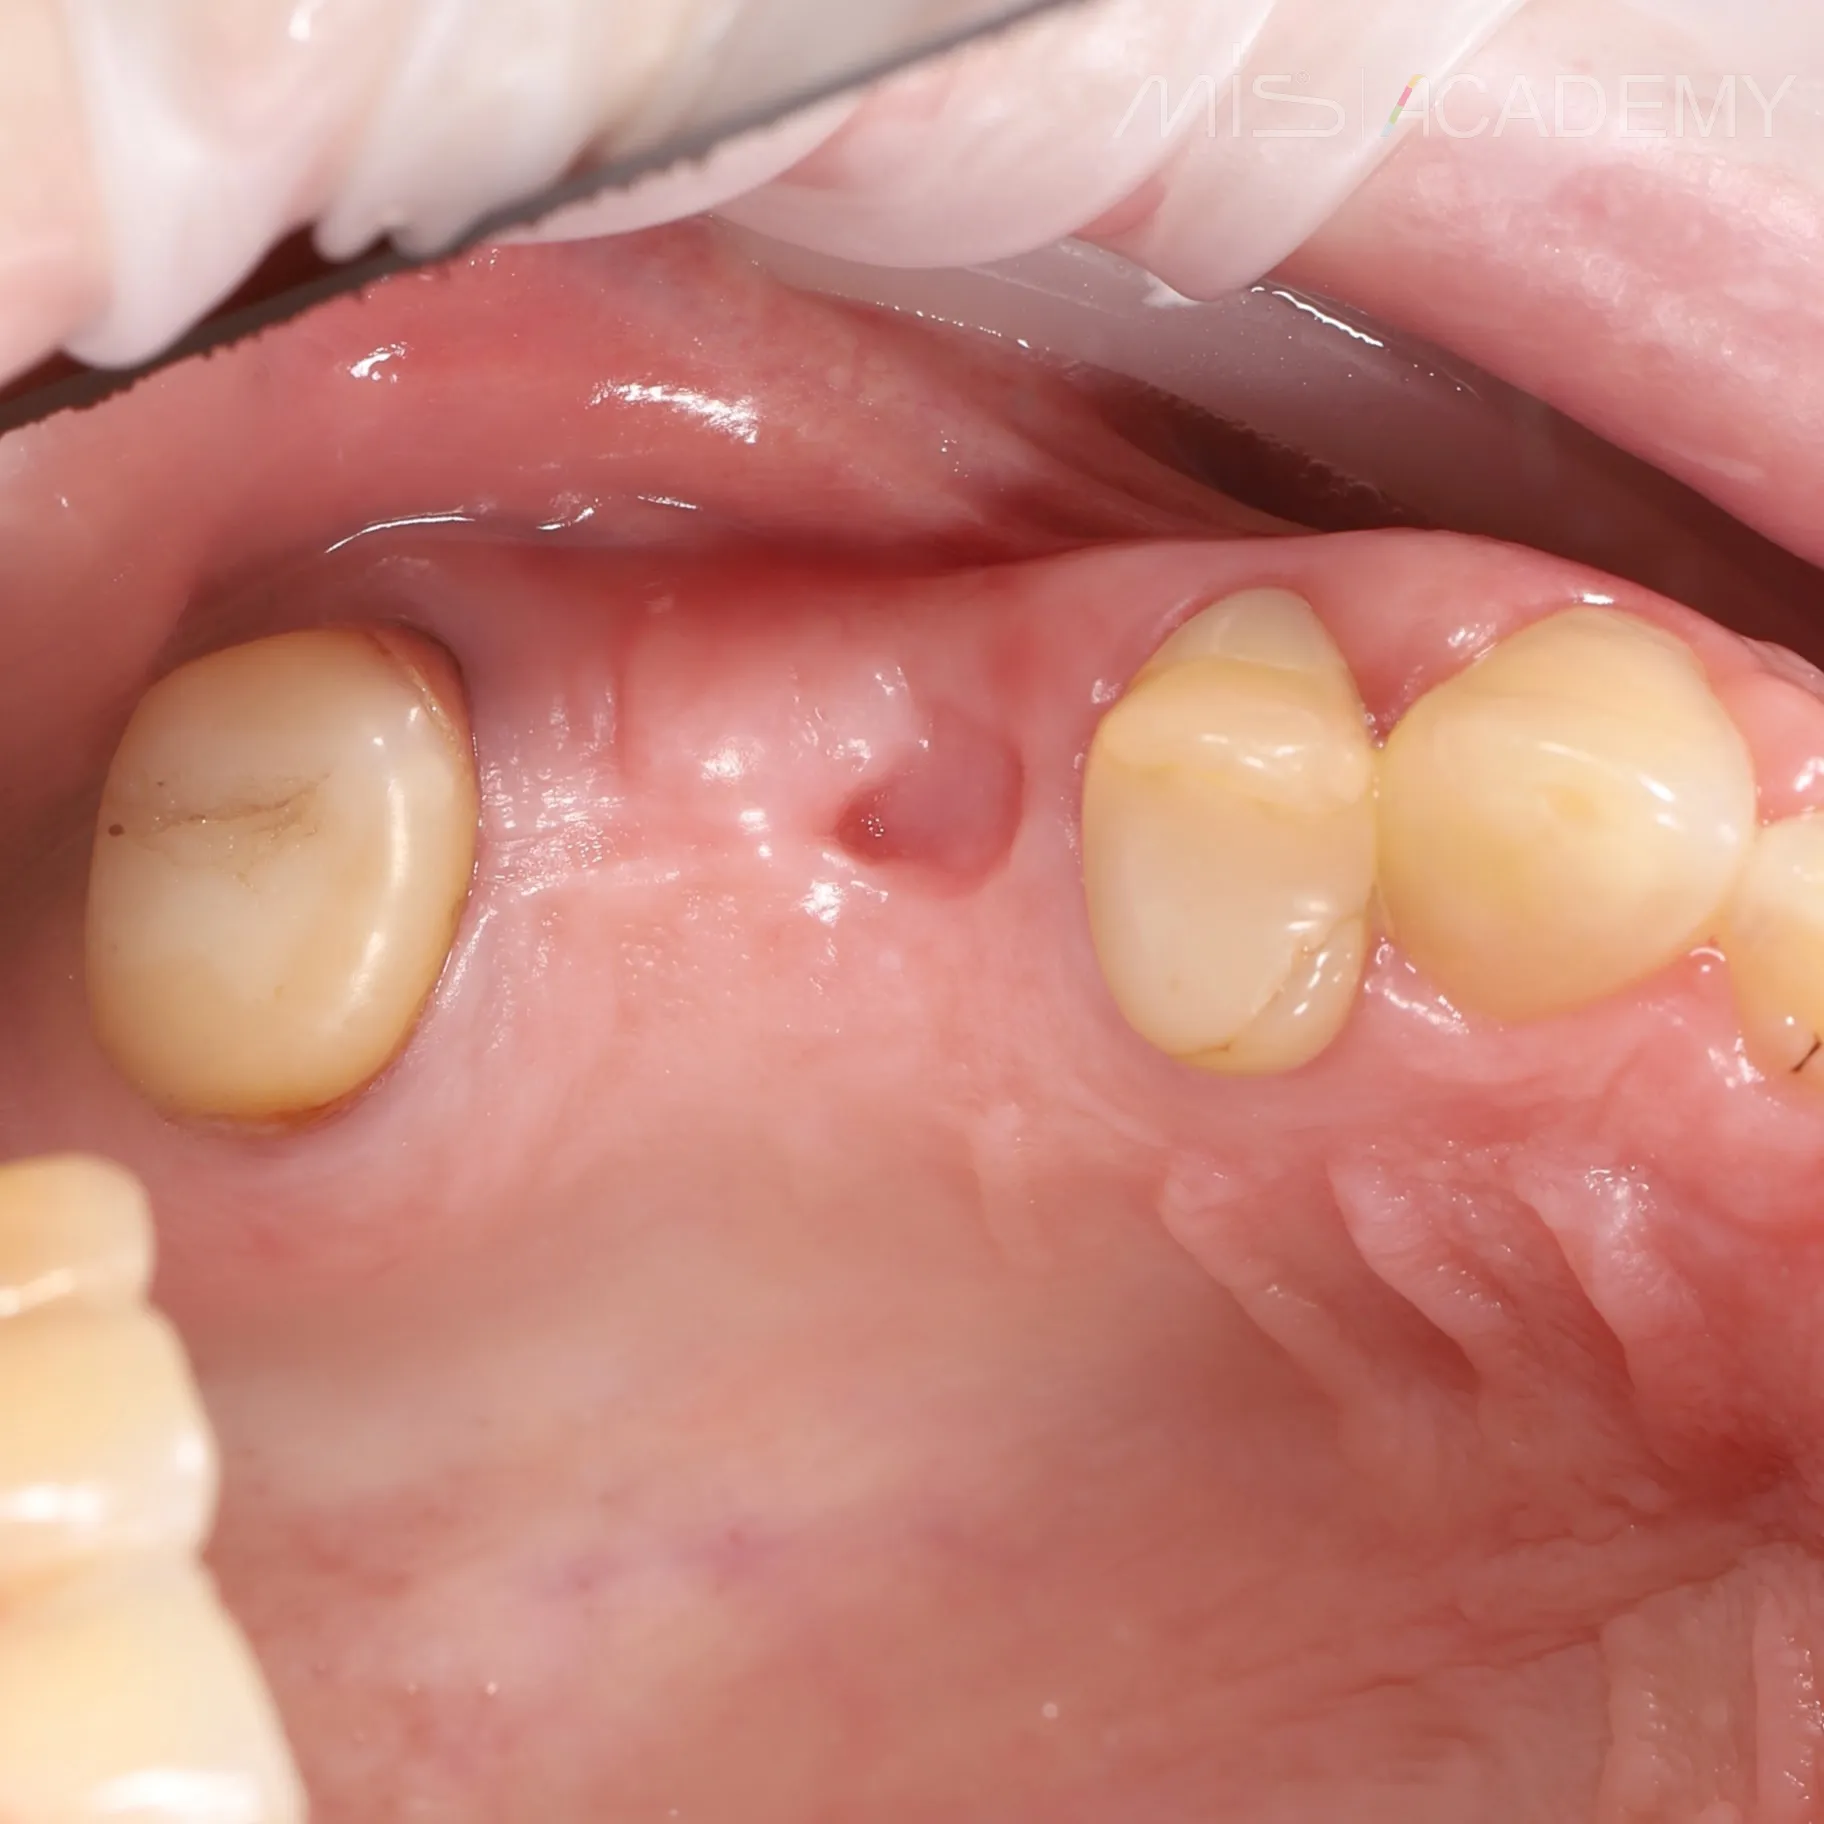

Произведено удаление зуба 2.4

P/S Заживление через 3 месяца.